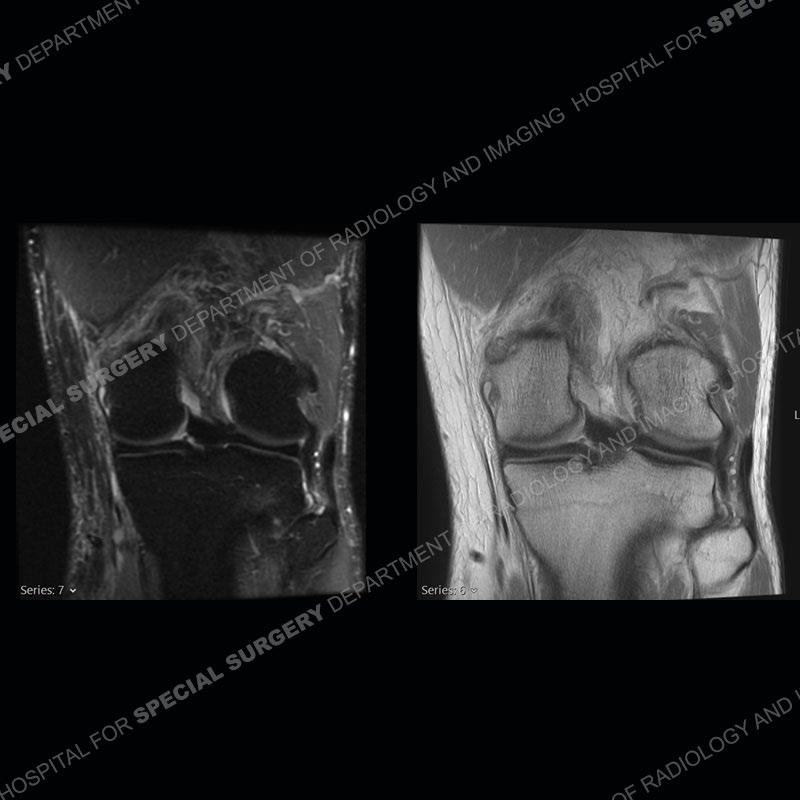

The radiographs show degenerative change of the medial compartment and a varus knee, but they are not germane to this case. No acute bony injury is present. The MRI shows edema of the posterior medial knee/soft tissue and a focal area of a partially disrupted low signal structure. The details are kept at a minimum in the findings of this case on purpose.

Diagnosis: Partial Disruption Medial Head Gastrocnemius (MHG)

The findings were kept purposefully vague as identifying the structures early on takes away a lot of the diagnosis. An uncommon entity and one of which we do not see a lot. Enthesopathic changes and tendinosis are seen as are distal MHG injuries, but proximal tears are rarely present. This case highlights a number of points. One, it almost always comes down to anatomy. Perhaps not a structure we normally spend too much time on, except save for diagnosing a Baker’s cyst, but knowing where this structure and all structures exist in all three planes is imperative. Second, when you think you are making a “call” or finding that you have never made before, step back and think is this just the abnormal presentation of a common pathology. That situation arises much more frequently. Third, if you look at it once, twice, and probably a third time and are confident in your odd or very rare diagnosis, stick to your guns. Especially, when it comes down to anatomic structures, the proof will be in the images.

Fourth, use all imaging planes and different pulse sequences to make your diagnosis. The edema highlighted in this case can be seen as the obscuration of fat on the PD images but is much easier to perceive as the high signal on the IR pulse sequences. The actual disruption of the MHG myotendinous junction is only able to be seen on the axial images. On the sagittal and coronal images, we get a sense something is wrong but hard to be exact. Lastly, when you look at a study and something just seems off (as I would say the sagittal and coronal images do with that dark band of tissue posteriorly), listen to yourself and go through the study slowly and meticulously. Most of the time you will find you were right, and something indeed is present.